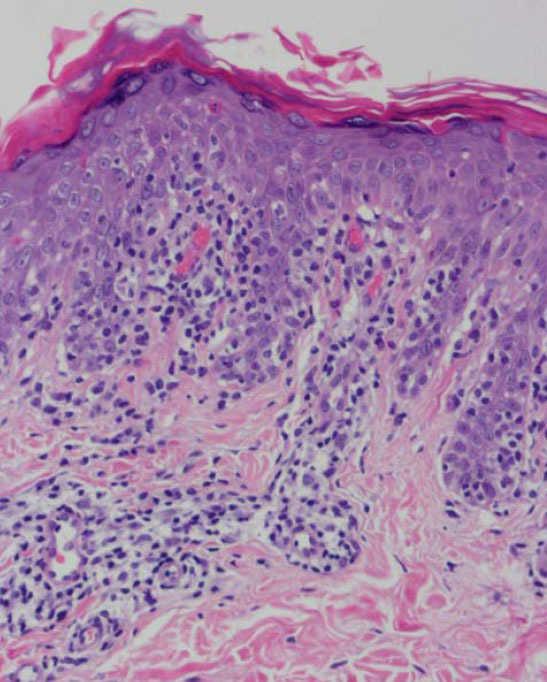

Se practicaron varias biopsias cutáneas, algunas de ellas sin alteraciones significativas. En otras se observó (figs. 4-6) una epidermis con hiperqueratosis y paraqueratosis focal, elongación de las crestas interpapilares y focos de degeneración hidrópica basal, con algún cuerpo apoptótico aislado. En dermis superficial y media existía un infiltrado linfocitario perivascular. Llamaba la atención la exocitosis de linfocitos atípicos intraepidérmicos, alguno de ellos con halo claro perinuclear y en alguna zona incluso iniciando la formación de microabscesos de Pautrier.

Como ocurrió con nuestro paciente, el estudio histopatológico en los estadios iniciales de la enfermedad puede ser muy inespecífico, lo que motiva además el retraso diagnóstico. En las fases más avanzadas revela la presencia de epidermotropismo de linfocitos anómalos, que a veces constituyen microabscesos de 5,6,8,11-23. En contraste con la micosis fungoide clásica, en esta variante parece que se observa un epidermotropismo más llamativo en contraste con un infiltrado linfocitario moderado en la dermis24.

Fig. 4.—Paraqueratosis focal, elongación de crestas interpapilares, focos de degeneración hidrópica basal. (Hematoxilina-eosina, ×40.)

Fig. 5.—Exocitosis intraepidérmica de linfocitos atípicos. (Hematoxi-lina-eosina, ×100.)